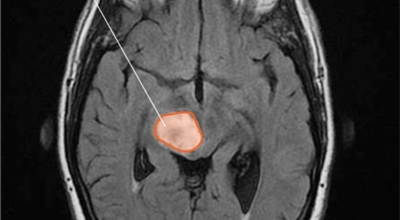

뇌종양

뇌종양이란 뇌 조직이나 뇌를 싸고 있는 막에서 발생한 종양과, 머리뼈나 주변 구조물로부터 멀리 떨어진 부위에서 뇌 조직이나 뇌막으로 전이된 종양을 의미해요. 뇌종양은 양성과 악성으로 나눌 수 있답니다. 양성 뇌종양은 성장 속도가 느리며 주위 조직과의 경계가 뚜렷해요. 양성 뇌종양은 수술 이외의 다른 치료 없이 완치되는 경우가 흔하고, 대부분 천천히 자라기 때문에 수술하지 않고 경과를 관찰하기도 해요.

악성 뇌종양은 뇌암이라고도 하고, 성장 속도가 빠르며 주위 조직으로의 침투 역량이 강해요. 이에 따라 정상 뇌 조직으로 침윤되고 정상 뇌 조직과의 경계가 불분명해서 치료가 어려운 편이예요. 악성 뇌종양은 주변의 정상 뇌 조직을 빠른 속도로 파괴해요.